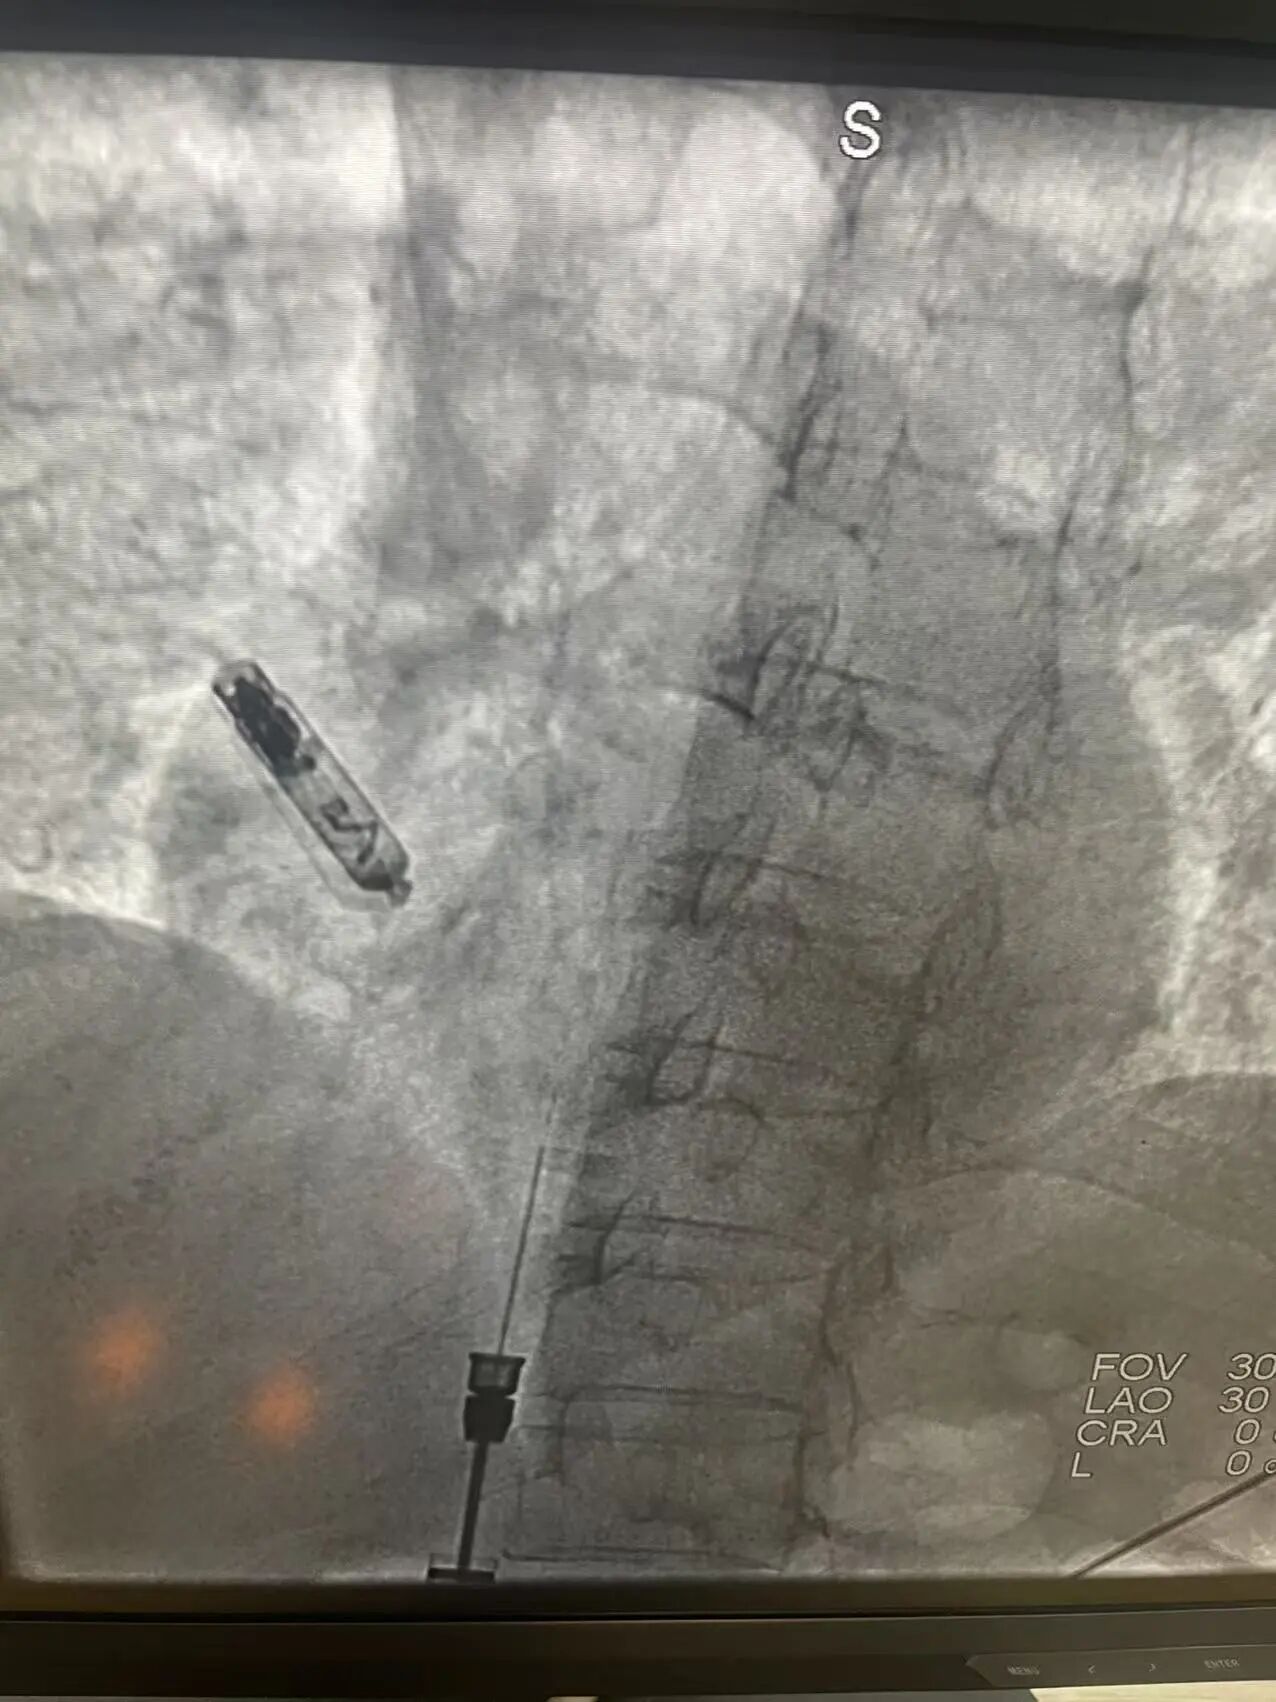

手术中,团队通过患者股静脉穿刺,将起搏器通过递送系统精准植入到患者右心房的理想位置。手术过程非常顺利,耗时短,术后患者感觉良好,几乎看不到手术疤痕,预计很快即可恢复日常活动。

其优势在于针对此类患者,能够实现更接近生理状态的心房起搏,可以更好的维持心脏的节律和功能,另外与传统起搏器手术需要在胸前皮下制作囊袋、植入脉冲发生器并经静脉放置导线不同,此次手术采用的Aveir AR心房无导线起搏器仅有维生素胶囊大小,重量仅约2克,无切口损伤,对生活质量有了极大的提高。